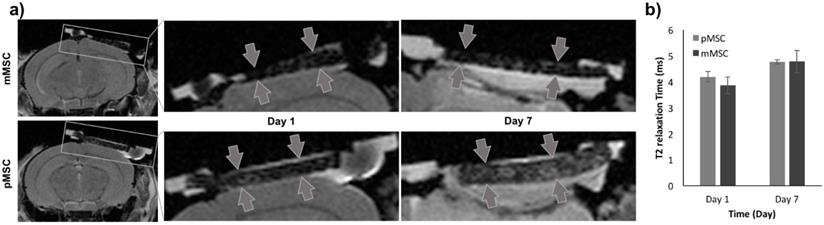

MRI to localize implanted Feru-AFC-labeled mMSCs and pMSCs in mouse calvarial defects. (a) Representative images from MRI of mouse (matched) and pig (mismatched) MSCs transplants (arrows) in calvarial defects, 1 and 7 days after implantation. (b) Corresponding quantitative analysis from MRI of matched and mismatched MSCs in calvarial defects (p > 0.05 for pMSCs versus mMSCs on days 1 and 7).

In Vivo Detection of Immune Rejection-induced Apoptosis of Pig MSCs

To evaluate the Feru-AFC NPs in vivo, we delivered them into mMSCs (matched) and pMSCs (mismatched) before transplanting them into female C57BL/6J mice with calvarial defects (n = 6). We used MRI to localize the Feru-AFC-treated mMSCs and pMSCs seeded in the scaffold (Figure 4a). In vivo MRI of the Feru-AFC NP-treated mMSC and pMSC transplants did not reveal any significant differences in T2 relaxation time at days 1 and 7 after implantation (p = 0.43 and p = 0.98, respectively) (Figure 4b).

While in vivo MRI enabled localization of cell transplants in skull defects on day 1, we did not observe significant signal differences between the matched (mMSCs) and mismatched (pMSCs) implants at day 7 post transplantation (Figure 4). In accordance with other studies,53 we showed that the iron oxide signal on MR images could persist after the death of labeled cells; this may be due to slow iron metabolism, macrophage/microglial behaviors, and/or our short follow-up period. The carboxymethyldextran is cleaved by dextranase and excreted by the kidneys. The iron core is incorporated into the bodies iron store and slowly metabolized over time. The T2-signal is not linearly related to iron concentration. The initially high local iron concentration at the transplant site likely decreased over time, but not enough to change the T2-value within the first 7 days. There is a possibility that the released irons are engulfed in the local macrophages and get degraded slowly.